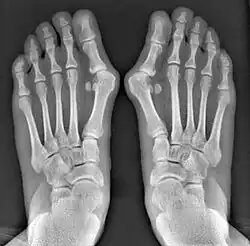

Normal foot skeleton

Fig 1a: Normal foot skeleton

First metatarsal bone has moved aside

Fig. 1b: First metatarsal bone has moved aside

Primus varus deformity is the leaning of the first metatarsal bone away from the second metatarsal and towards the opposite foot (Fig. 1). As it leans over, its head sticks out to form the bunion bump and it also widens the forefoot to cause shoes feeling too tight. Thus when bunion pain becomes unmanageable, surgical correction is to narrow the forefoot by repositioning of the first metatarsal head back to its normal position. This can be done by osteotomy (bone-breaking), soft tissue (non-osteotomy) or fusion techniques.